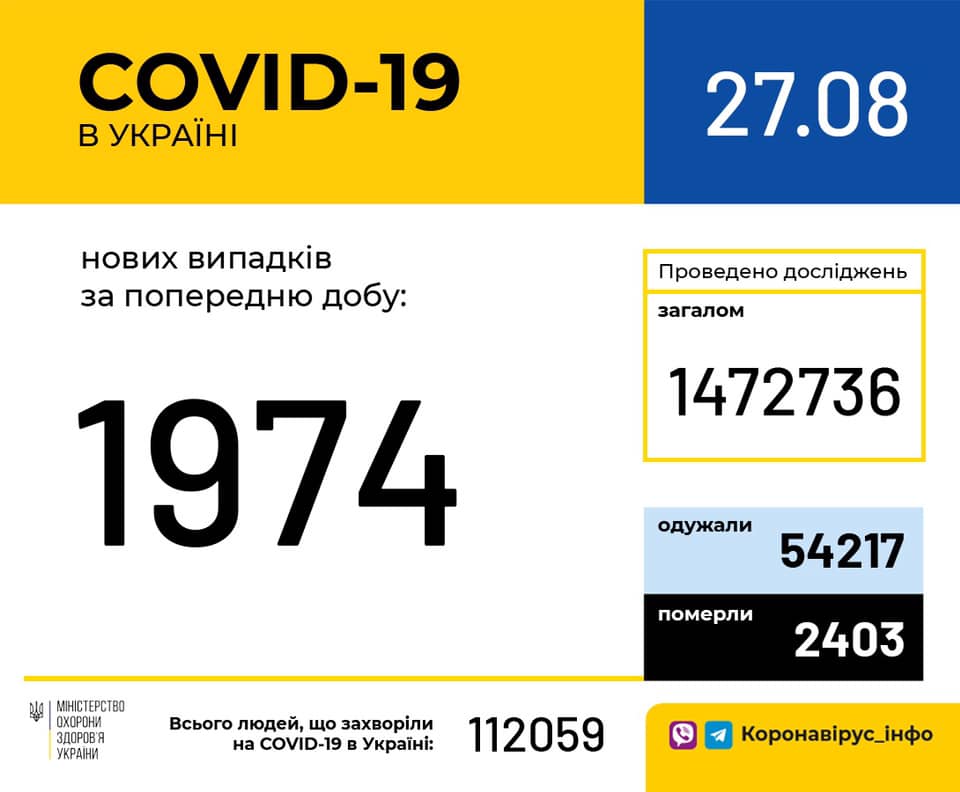

Більше 3 тисяч випадків захворювання на коронавірус зафіксували в Україні за добу

11.09.2020 09:37